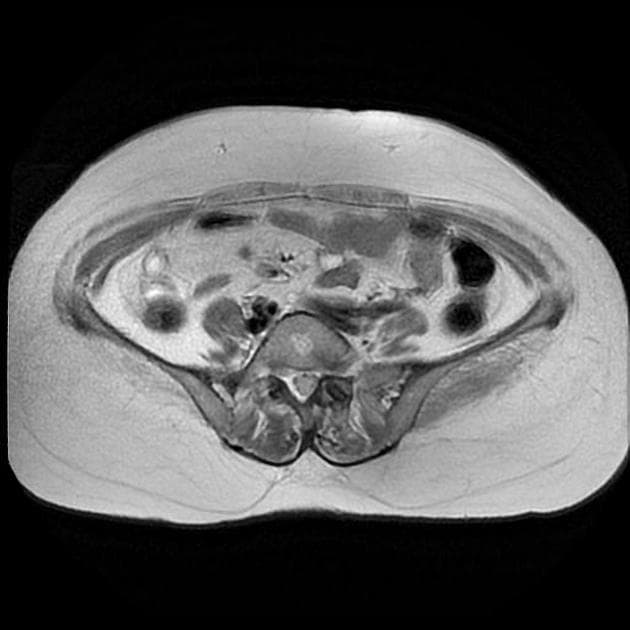

Axial C+ arterial phase

- Khối hình bầu dục ở thuỳ trên bên trái, các hình ảnh còn lại bình thường.

- Khối ở thuỳ trên bên trái, vị trí trong trung thất, có vôi hóa một phần, tiếp giáp với màng phổi trung thất và động mạch dưới đòn trái, không có xâm lấn hoặc bao quanh mạch máu (no invasion or vascular encasement).

- Nốt mô mềm không vôi hóa liền kề (adjacent non-calcified soft tissue nodule).

Ca lâm sàng này thể hiện cả di căn phổi có vôi hóa và không vôi hóa từ u sụn xương chi (appendicular osteosarcoma).

Di căn phổi vôi hóa – u sụn xương (calcified lung metastasis - osteosarcoma)

Ca lâm sàng này thể hiện cả di căn phổi có vôi hóa và không vôi hóa từ u sụn xương chi. Sự hiện diện của vôi hóa trong tổn thương di căn gợi ý về nguồn gốc u sụn xương. Nốt mô mềm không vôi hóa liền kề với khối vôi hóa có thể là một tổn thương di căn khác hoặc một quá trình lành tính.